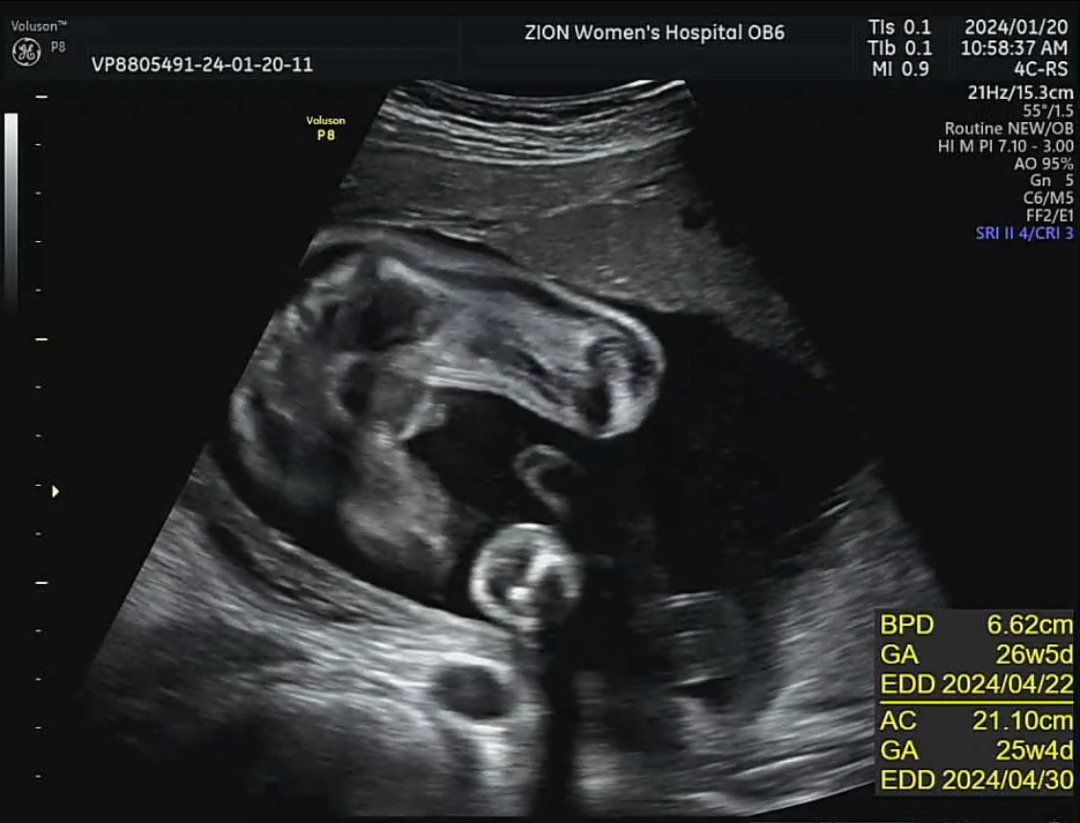

26주0일 아들 초음파💙

오늘 임당 검사 후 초음파로 아가 확인했어용! 저기 가운 데 있는 게… 🌶️…? 성별 반전 언급 없으셨으니 아들 맞겠쥬..?ㅎㅎ

아들 확실하네용

아들맘 추카해용! 이시기에는 반전없어욤!